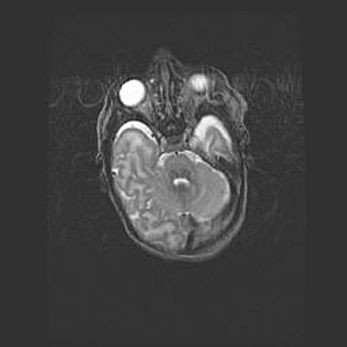

Неполная лизэнцефалия (пахигирия). Открытая гидроцефалия.

Возраст: 17 дней

Вес: 3110 г

Пол: мужской

Окружность головы: 33,5 см

Срок гестации: 35-36 недель

Лизэнцефалия—недоразвитие корковой пластинки и мозговых извилин в результате нарушения миграции нейронов коры. Поверхность мозговых полушарий гладкая. Микроскопически выявляется отсутствие нормальных слоев коры и скопление групп нейронов в подкорковом белом веществе.

Пахигирия—уменьшение числа вторичных извилин. В пораженном полушарии нервные клетки образуют толстый недифференцированный слой с неправильно расположенными нервными волокнами и группами гетеротопных клеток. Нервные клетки незрелые. Белое вещество истончено. При этом нередко аномально развит корково-спинномозговой путь.